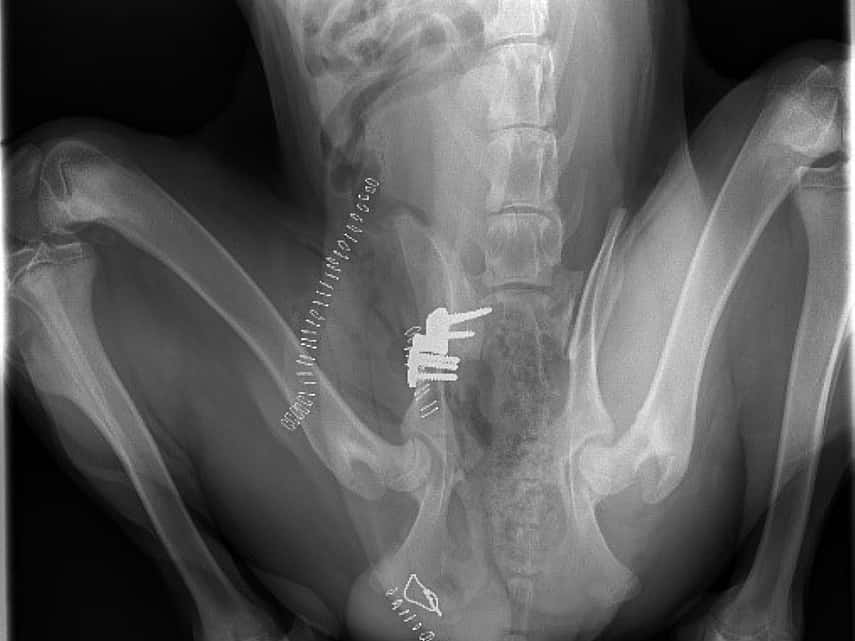

Nadat we een RX hadden genomen, zagen we dat Ramses leed aan bilaterale heupdysplasie. Beide heupen lagen bijna volledig uit de kom. Dankzij het snelle ingrijpen van zijn baasjes en gezien zijn jonge leeftijd had Ramses gelukkig nog geen artrose.

Daadoor konden we kiezen voor een TPO: Triple Pelvic Osteotomie. Bij deze operatie wordt het bekken op drie plaatsen doorgezaagd waardoor we de heupkom kunnen kantelen.

De dubbele groene streep geeft de plaats aan waar de osteotomie moet gebeuren

Het orthopedisch materiaal

Het plaatje wordt gekozen